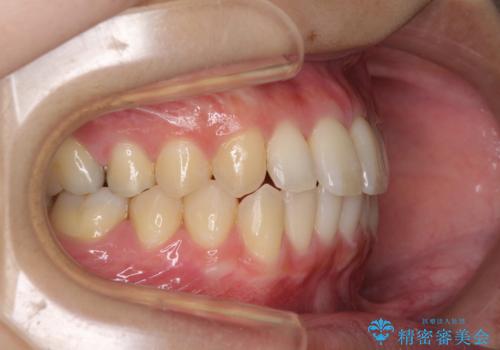

治療期間が世界的な感染症の流行時期と重なったため、海外と日本での往来が困難となり、治療継続が懸念されました。

それでも、しっかりとマウスピースを装着してくださったので、大きなトラブルもなく治療を終えることができました。